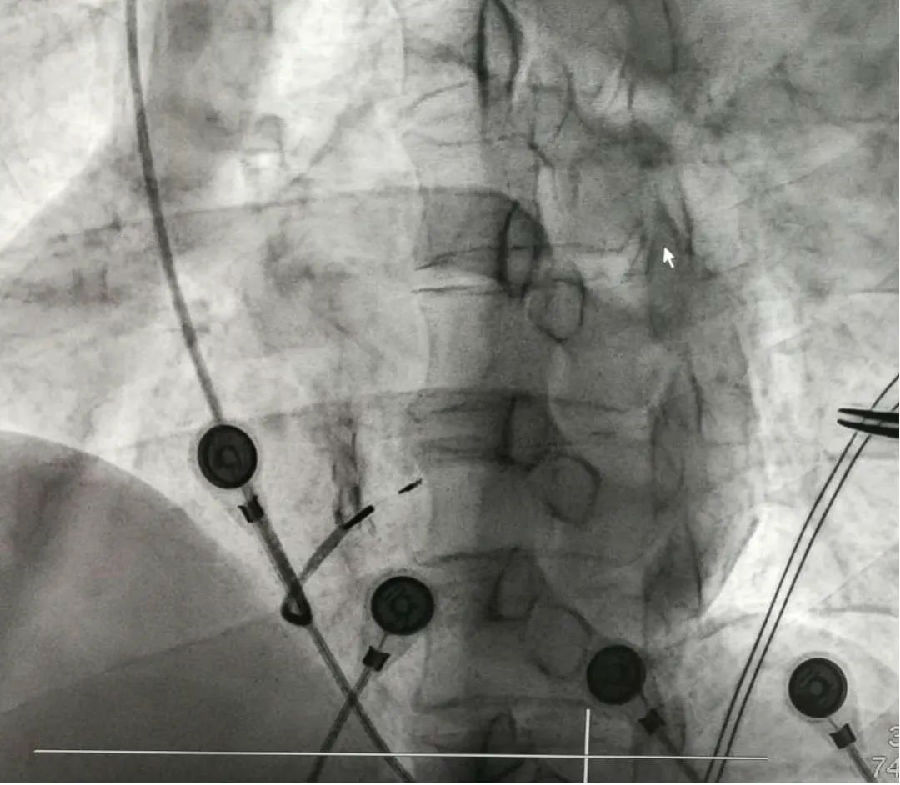

因左束支区域起搏在漯河地区尚属首例,考虑术中、术后可能出现的各种风险,在充分的术前准备下,刘东亮教授带领心脏中心电生理团队成功为患者植入左束支区域起搏永久起搏器,测试各种参数满意,助患者转危为安。

起搏器植入左束支区域

刘东亮教授说,起搏器的发明成功解决了人类心跳变慢的问题,可以使心脏正常地跳动起来,挽救患者的生命。随着对心脏起搏部位研究的不断深入,左束支区域起搏是一项接近生理性起搏的新技术,目前的研究发现它能在较大限度维持起搏器的基础上保持左室电同步,不仅可以让患者恢复正常心跳,还可以减少甚至改善心衰的发生。